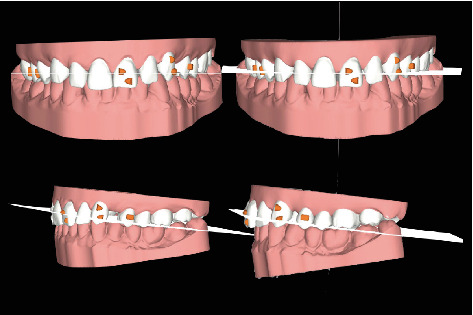

The orthodontic treatment of the upper arch alone was carried out using transparent aligners (Figure 4), in order to redistribute the diastemas present in the superior frontal group so as to uniform the spaces, center the medians, and facilitate the subsequent prosthetic rehabilitation of the same. In addition to aligning the upper frontal group from 13 to 23, derotation of the 23 and correction of the distal tipping were performed.

Figure 4.

Orthodontic treatment plan with the Invisalign® software. On the left, the initial situation (frontal and lateral view) and, on the right, the case at the end of the orthodontic treatment.